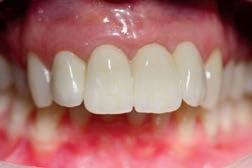

60 Top Dentists 2025

The annual Top Dentist list showcases excellence in dental care. See which New Hampshire dentists were voted by their peers as the most trustworthy.